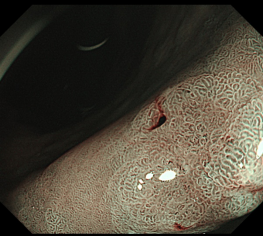

科室高清晰胃肠镜:正常的胃窦(线圈样腺管)和食管粘膜放大观察(IPCL)

消化道早癌的病例展示(经内镜手术或活检证实):

胃角的腺癌

胃窦的微小腺癌

胃窦印戒细胞癌

十二指肠降段早癌